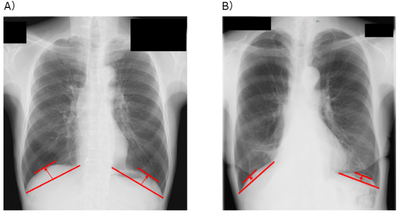

そこで研究グループは、胸部X線画像から簡便に測定できる横隔膜の位置の高さである「横隔膜ドーム高※3」という指標に注目しました。横隔膜ドーム高は、肺機能や運動耐容能と密接に関連することが明らかになっており、より簡便かつ患者に負担なく術後予後を予測する指標となる可能性があります。しかし、これまで肺がん患者において、横隔膜ドーム高と術後の予後との関連性は明らかにされていませんでした。

研究グループは、近畿大学病院において肺がんの肺葉切除術を受けた患者を対象に、術前1カ月以内に撮影された胸部X線画像を用い、肺腫瘍側の横隔膜ドーム高を測定しました。その結果、多変量解析※5 において、術前の横隔膜ドーム高は術後予後に影響を及ぼすことが知られている喫煙状況、肺機能、がんのステージなどの因子の影響を受けず、独立した術後予後を予測できる因子であることが明らかとなりました(HR=2.10、p<0.01)。さらに、時間経過に伴う生存率の推移を示すカプラン・マイヤー生存曲線※6 による解析では、横隔膜ドーム高が低い患者群において、3年間の全生存率※7 が有意に低く(p<0.01)、加えて肺炎や呼吸不全などの呼吸器疾患による死亡に限定した場合でも、3年の疾患特異的生存率※8 が有意に低いことが示されました(p<0.01)。これらの結果から、横隔膜ドーム高が低い患者群に対する術前呼吸リハビリテーションは、術後予後改善へ向けて重要である可能性が示唆されました。

※3 横隔膜ドーム高:横隔膜がどれくらい上に持ち上がっているか(高さ)を示す指標。